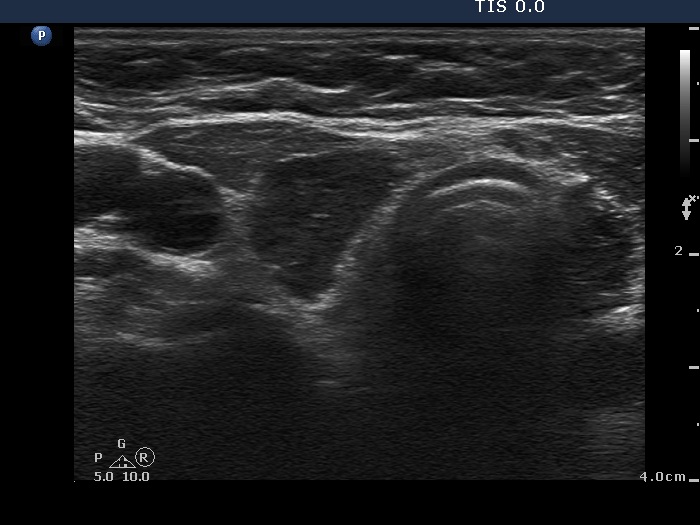

Ultrasonography. Both lobes were composed of a central hypoechogenic part surrounded with an echonormal rim. Although this pattern resembles that of a large hypoechogenic nodule occupying almost the entire lobe, this is one of the characteristic presentations of Hashimoto's thyroiditis. In contrast with a nodule, the borders between the central hypoechogenic area and the surrounding echonormal rim are irregular.